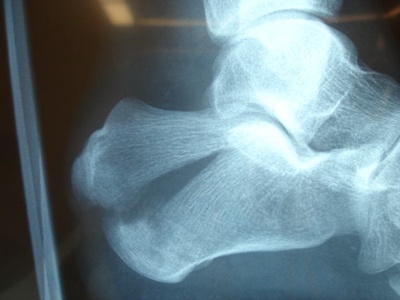

Talus

Talus connects leg to foot, transmitting body weight into the foot via subtalar and ankle joints. It has limited vascular supply, ossifies early, and fractures carry high avascular necrosis and arthritis risk.